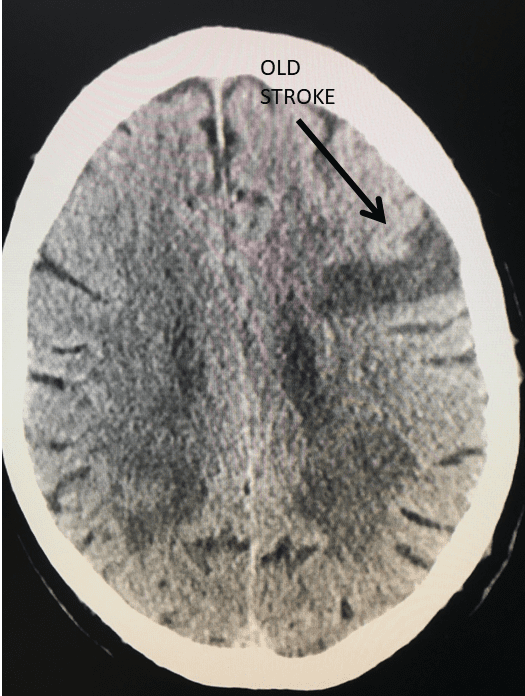

Brain:

74 Year Old Woman with Occipital Headaches

Author: Michael Brisman M.D., F.A.C.S., Read More!